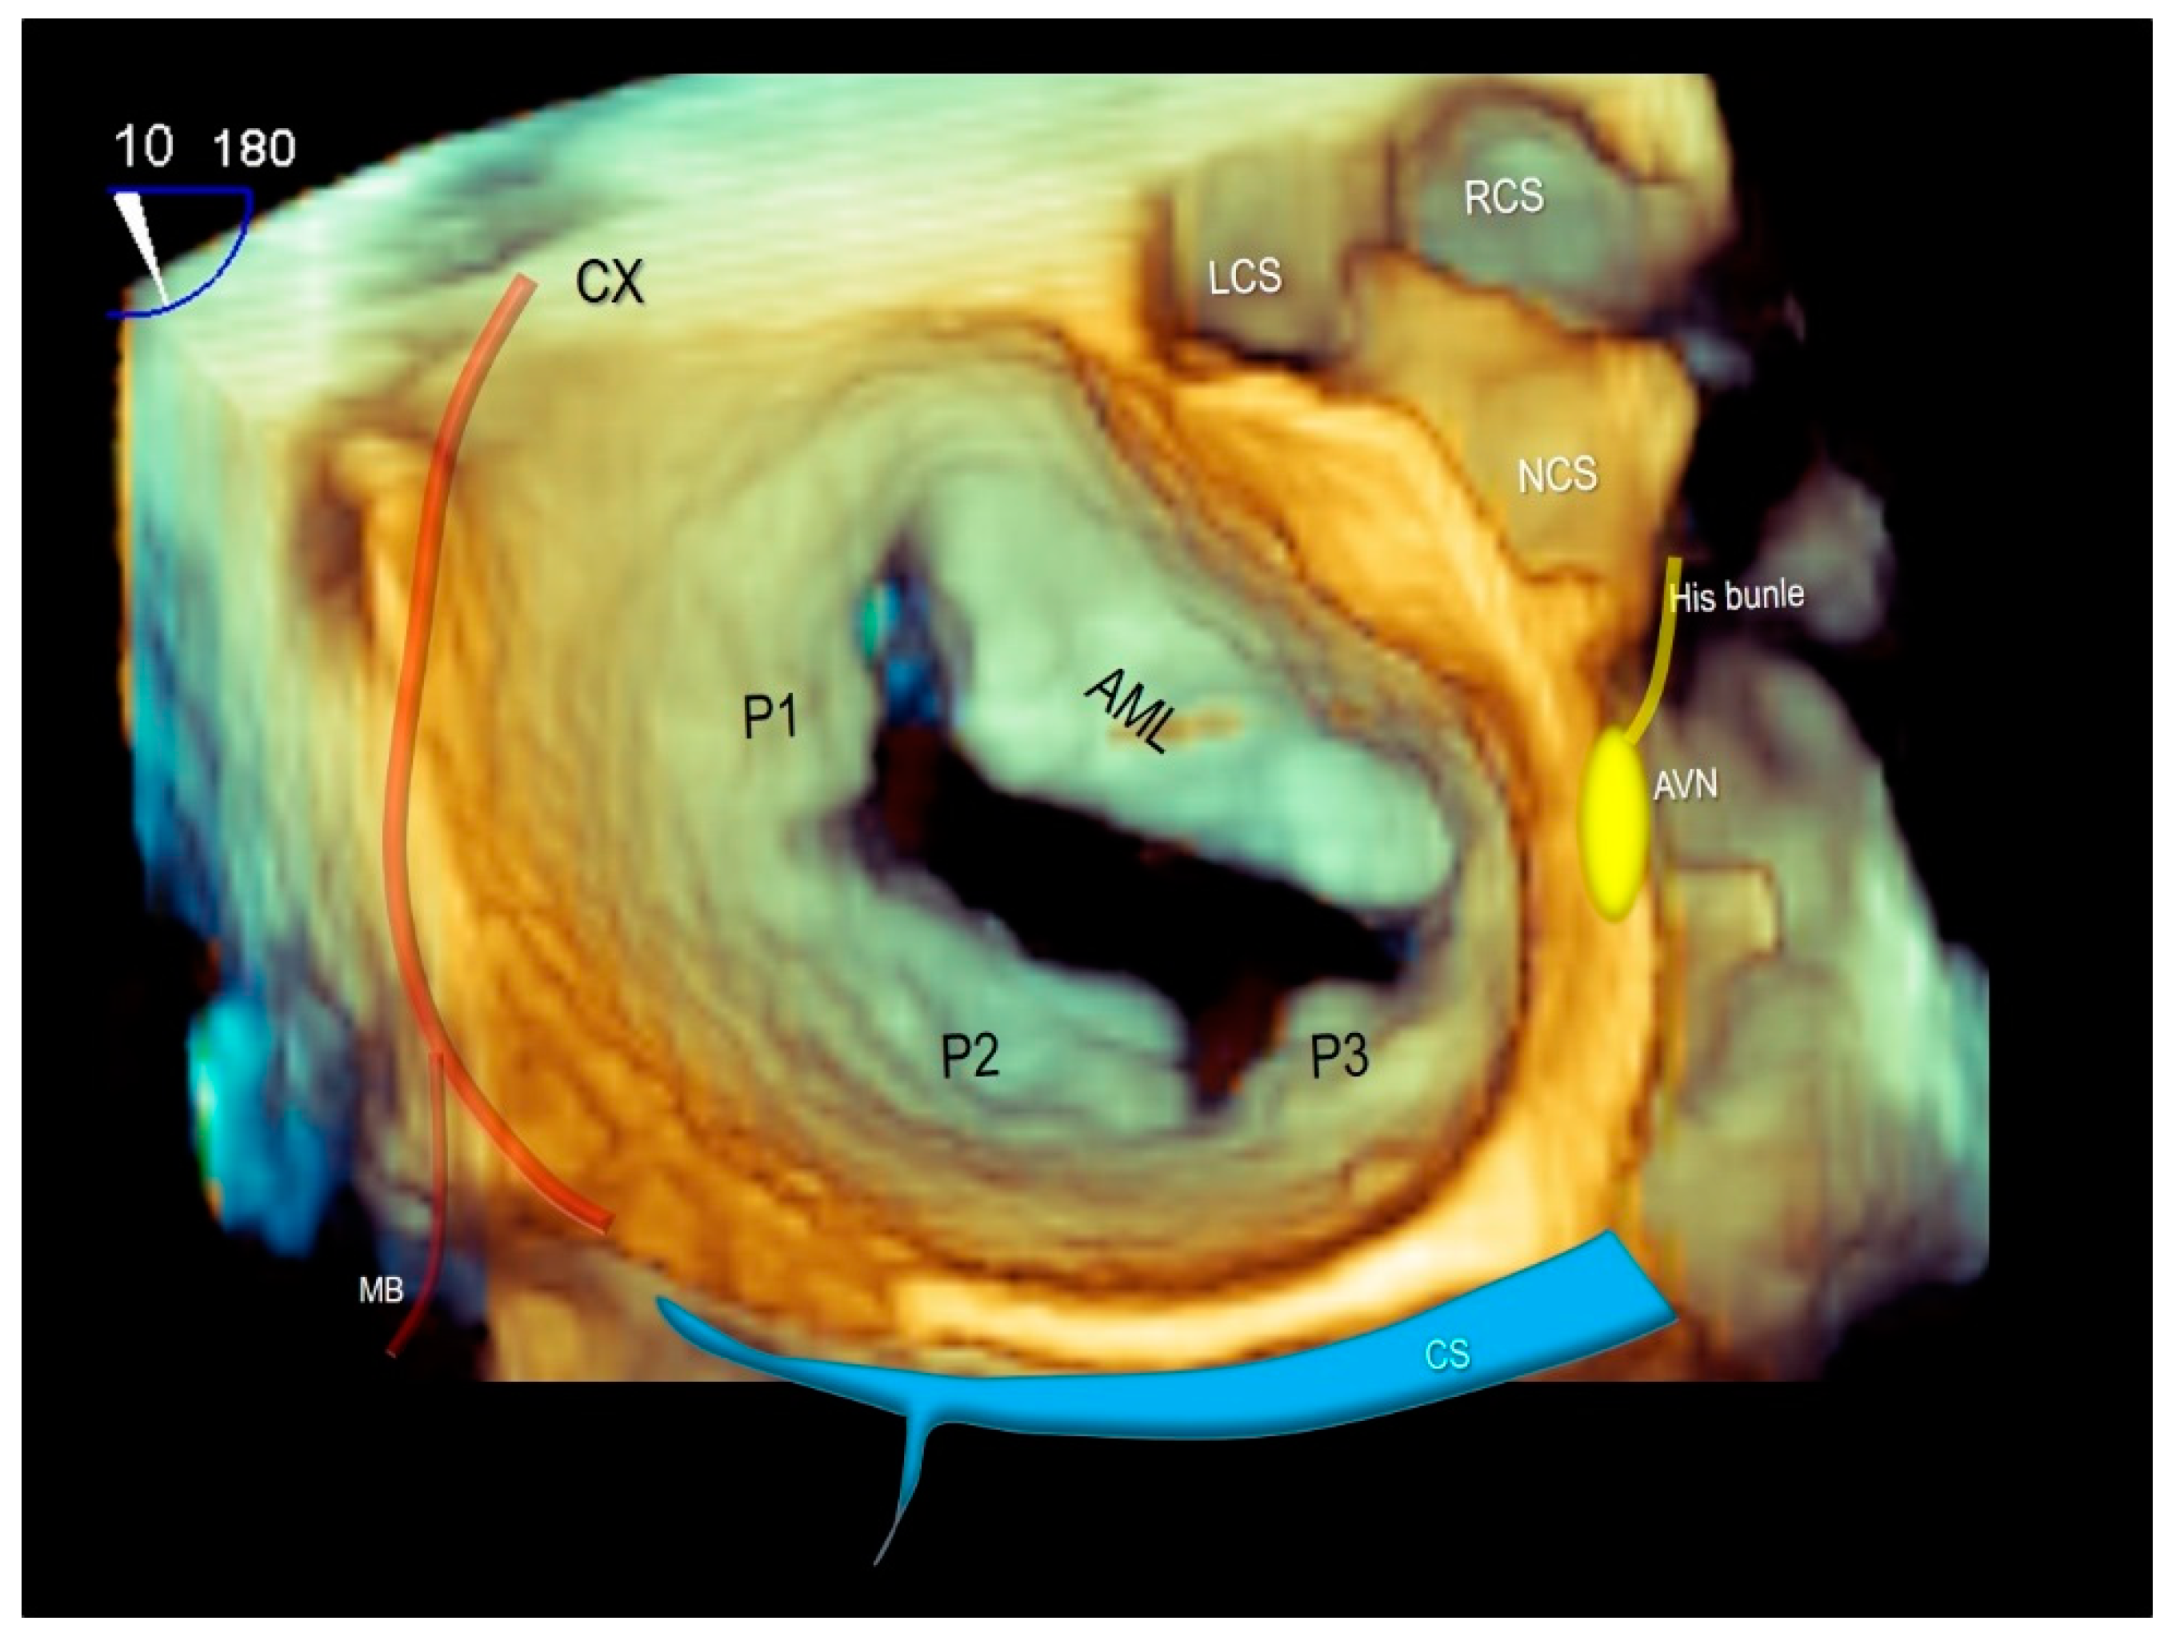

4. Chordal Apparatus

7. Surgical and Interventional Implications